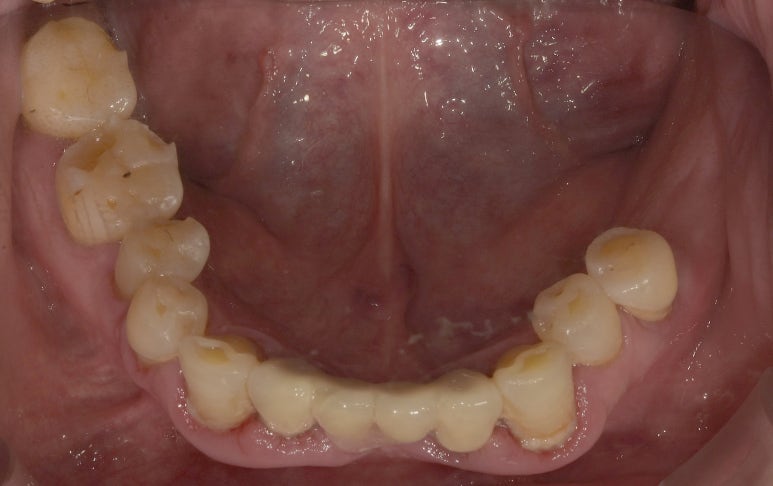

임플란트브릿지 치료전

2023-03-24

기존 환자분의 당부의 말씀과 함께 내원해주신 환자분은 보시는 바와 같이

왼쪽 아래 어금니 3개, 오른쪽 위 어금니 1개를 이미 상실하신 상태에서 내원해 주셨습니다.

우선 우리 환자분 가장 시급한 치료는 왼쪽 아래 어금니 부분이었는데요.

아무래도 치아가 3개 결손되어있다보니 이대로 계속해서 방치할 경우

위아래 맞물리는 치아가 없어 상악 어금니가 점점 아래쪽으로 이동할 가능성이 있고,

그렇게 되면 치아 상태는 더 안좋아져 식사하는데 큰 불편함이 있을 수 있기 때문에 빠르게 임플란트로 치료 계획을 세웠습니다.

결손된 치아는 3개이지만, 임플란트는 양 옆 2개만 식립하고 중간은 파닉(폰틱, pontic)이라고 하는

가짜 치아로 연결해 브릿지 형태로 치료하는 것이 환자분의 고생을 덜 수 있고

치료 비용 또한 절감할 수 있는 방안이기에 임플란트브릿지로 치료하기로 했습니다.